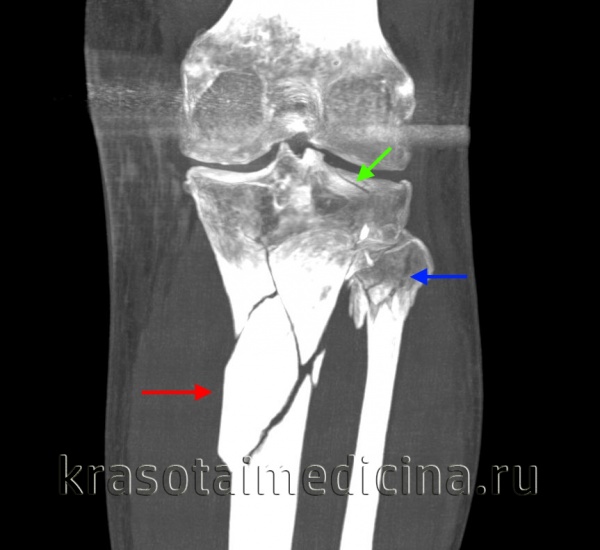

КТ коленного сустава и голени. Оскольчатый перелом большеберцовой кости в верхней трети диафиза (красная стрелка), перелом головки малоберцовой кости (синяя стрелка), перелом латерального мыщелка большеберцовой кости (зеленая стрелка).